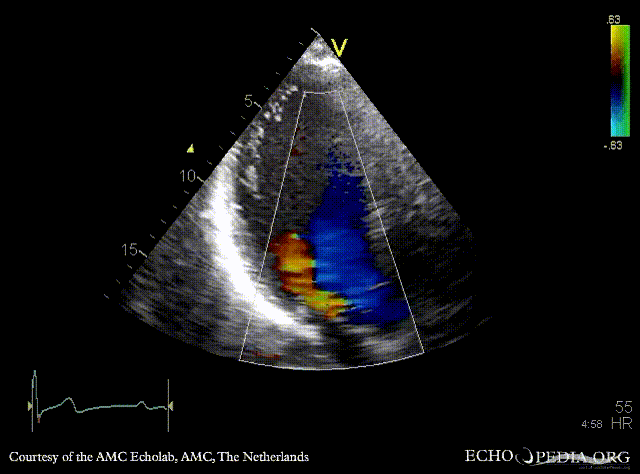

E00235.jpg

Subcostal view: pulsed-wave Doppler signal from abdominal aorta: diastolic flow reversal